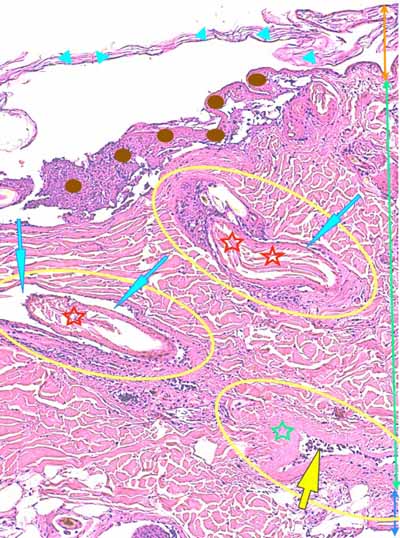

Photo 3 (Hémalun Eosine X 100) : l’épiderme se désengrène, une vésicule

sous-épidermique se forme. Le derme superficiel est œdémateux. Deux plages cellulaires dermiques

sont en étroit rapport avec des annexes folliculo-sébacées, dont une apparaît rompue.

Légendes de la Photo 3 :

- Ovales jaunes : plages cellulaires inflammatoires dans le derme périannexiel

- Flèche turquoise : follicule pileux rompu en rapport avec une plage inflammatoire

- Flèches jaunes : épiderme fragilisé qui se désengrène du derme

- Double flèche orange : épaisseur épidermique

- Double flèche verte : épaisseur dermique

- Double flèche bleue : épaisseur hypodermique

- Flèche orange : une vésicule sous-épidermique se forme